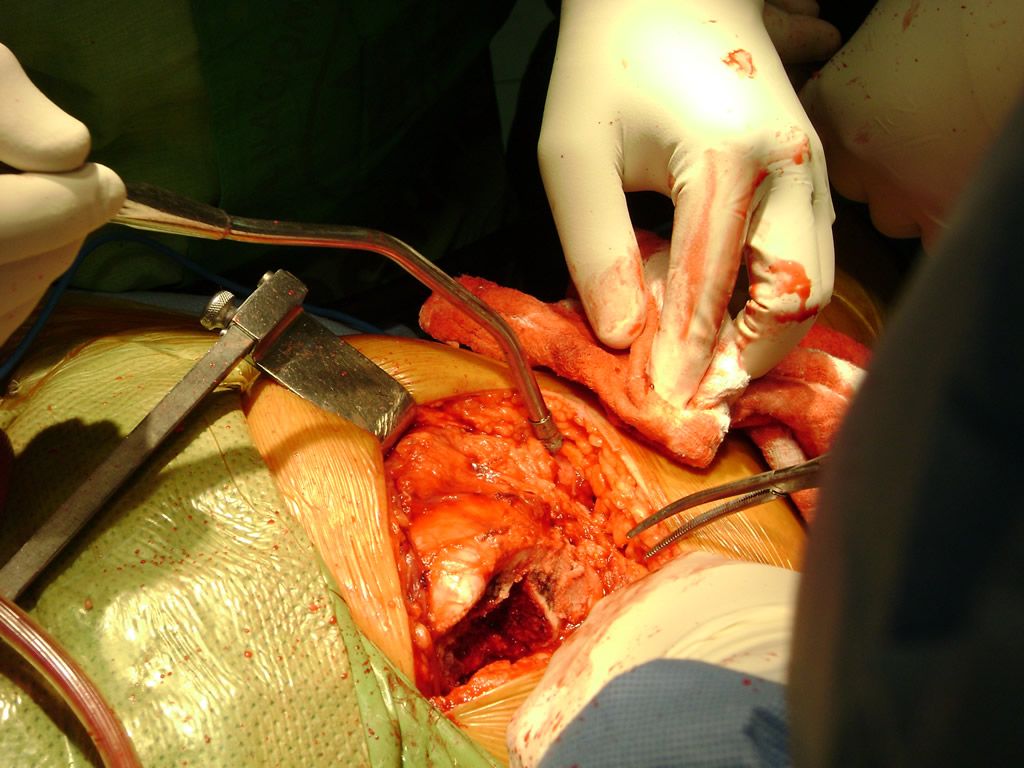

Cirugias en El Salvador - Perone y Tibia

Debido a la fina cobertura de piel que recubre la tibia y el peroné, las fracturas generalmente son abiertas, es decir, el hueso roto rasga la piel, atravesándola. Las fracturas de tibia y peroné generalmente se producen por un fuerte impacto o torsión.

De esta forma nos ponemos a tus órdenes, somos conocedores de estos tipos de problemas, visitarnos será un gusto el poderte ayudar. cualquier inquietud puedes escribirnos al correo Esta dirección de correo electrónico está siendo protegida contra los robots de spam. Necesita tener JavaScript habilitado para poder verlo.